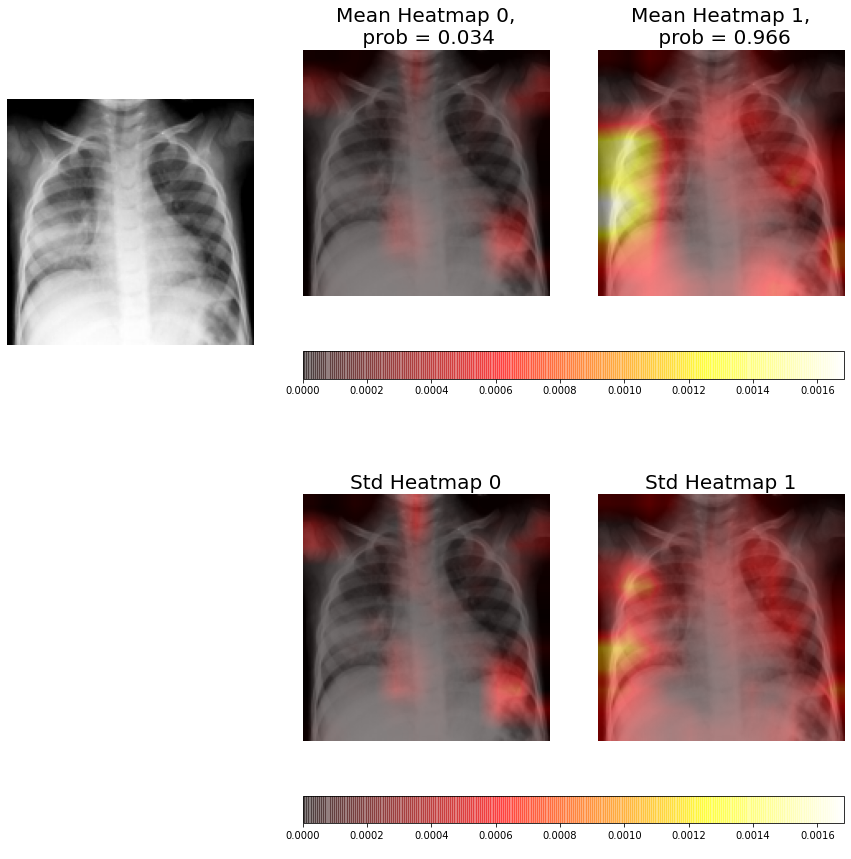

Figure 7 shows that there are signs of consolidation in the left lung. We can observe how both the probability estimated by the CNN model, 98.7%, and the heatmap corresponding to the consolidation class show that the system has correctly classified the radiography. However, we can see how the heatmap only marks the left side of the consolidations area, which does not cover all the consolidation signs. We can conclude that the CNN model has correctly classified the sample but it has not found all interesting area of the image.

The ensembles are composed by five individual CNNs, therefore, for each radiography we have five different heatmaps for each class (consolidation / non-consolidation). This allows us to compute the average heatmap and the uncertainty at each pixel (standard deviation at each pixel) for each class.

In Figures 9-11 we can see from left to right, and from top to bottom, the original X-ray, the average heatmap for the "non-consolidation" class, the average heatmap for the "consolidation" class, and the standard deviation heatmaps.

This visual representation provides to medical staff with relevant information. Firstly, the probabilities of each class predicted by the model are shown in the title of each average heatmap. Secondly, the average heatmaps show the areas of the X-rays that are most informative according to the ensemble. Finally, the standard deviation heatmaps provide information about the areas of greatest disagreement among individual CNNs (that is, the areas with the greatest uncertainty). This suggests that medical staff should pay more attention to areas with higher values in the average heatmaps and in the standard deviation heatmaps.

Figure 11 shows that the X-ray has consolidation signs in the left lung. The average heatmap marks practically all area affected by the pathology, unlike the visualization of an individual CNN that only marks a small part of the affected area. We can also observe how the standard deviation heatmap for neuron 1 indicates the adjacent areas to the one of interest. The probability of this class (consolidation) is 96.6%, lower than the obtained by individual CNN (98.7%), this is because the result is obtained from the average of the five models and not all of them have to present the optimal results, however by obtaining the average of all the models we increase the robustness of the model.